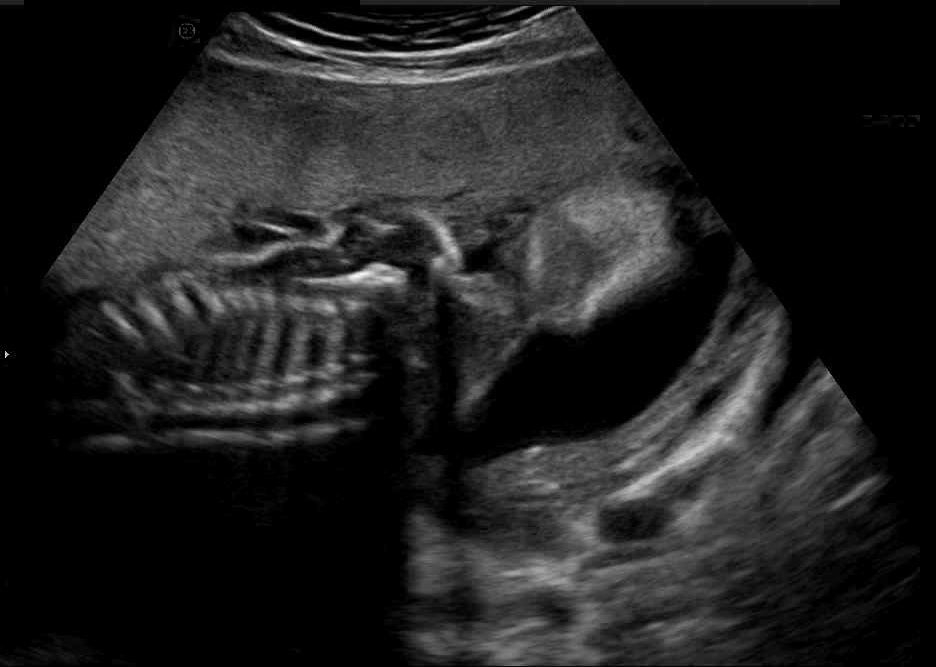

US simulation. We used a ray-tracing framework to render B-mode images from a geometric fetal model, by simulating a convex probe placed at multiple locations and orientations on the abdominal surface, with imaging settings listed in Tab 1. At each location, simply rasterizing a cross-section through the triangulated anatomical surfaces at the ultrasound center imaging plane provided corresponding semantic maps. Fig. 3 shows example B-mode images with corresponding semantic maps. A total of simulated frames were resized to and randomly split into training-validation-test sets by 80-10-10%.

In Fig. 3 we show that only learning an auxiliary seg-to-real translation, i.e. CUT+S, cannot guide the network to learn the semantics of simulated images.

CUT+SC with the loss term largely reduces hallucinated image content, although it still fails to generate fine anatomical details. With the multi-domain conditional generator and additional losses of ConPres, translated images preserve content and feature a realistic appearance. Training without leads to training instability.

Comparison to state-of-the-art. As seen qualitatively from the examples in Fig. 3, our method substantially outperforms the alternatives in terms of content preservation, while translating realistic US appearance. CycleGAN, SASAN, and CUT hallucinate inexistent tissue regions fail to generate fine anatomical structures, e.g. the ribs. StarGAN fails to generate faithful ultrasound speckle appearance, which leads to highly unrealistic images. Our method ConPres preserves anatomical structures, while enhancing the images with a realistic appearance. It further faithfully preserves acoustic shadows, even without explicit enforcement. However, as seen from the last column, the refraction artefact appears artificial in the images translated by all the methods. Note that although the imaging field-of-view (FoV) and probe opening in the simulation is significantly different from the real in-vivo images (Fig. 2) used for training, our ConPres maintains the input FoV closely compared to previous state-of-the-art. The results in Tab 2 quantitatively confirm the superiority of our method. Note that SSIM and FID/KID are used to measure translation performance from two different and sometimes competing aspects, with the former metric for quantifying structure preservation and the latter metrics for image realism.